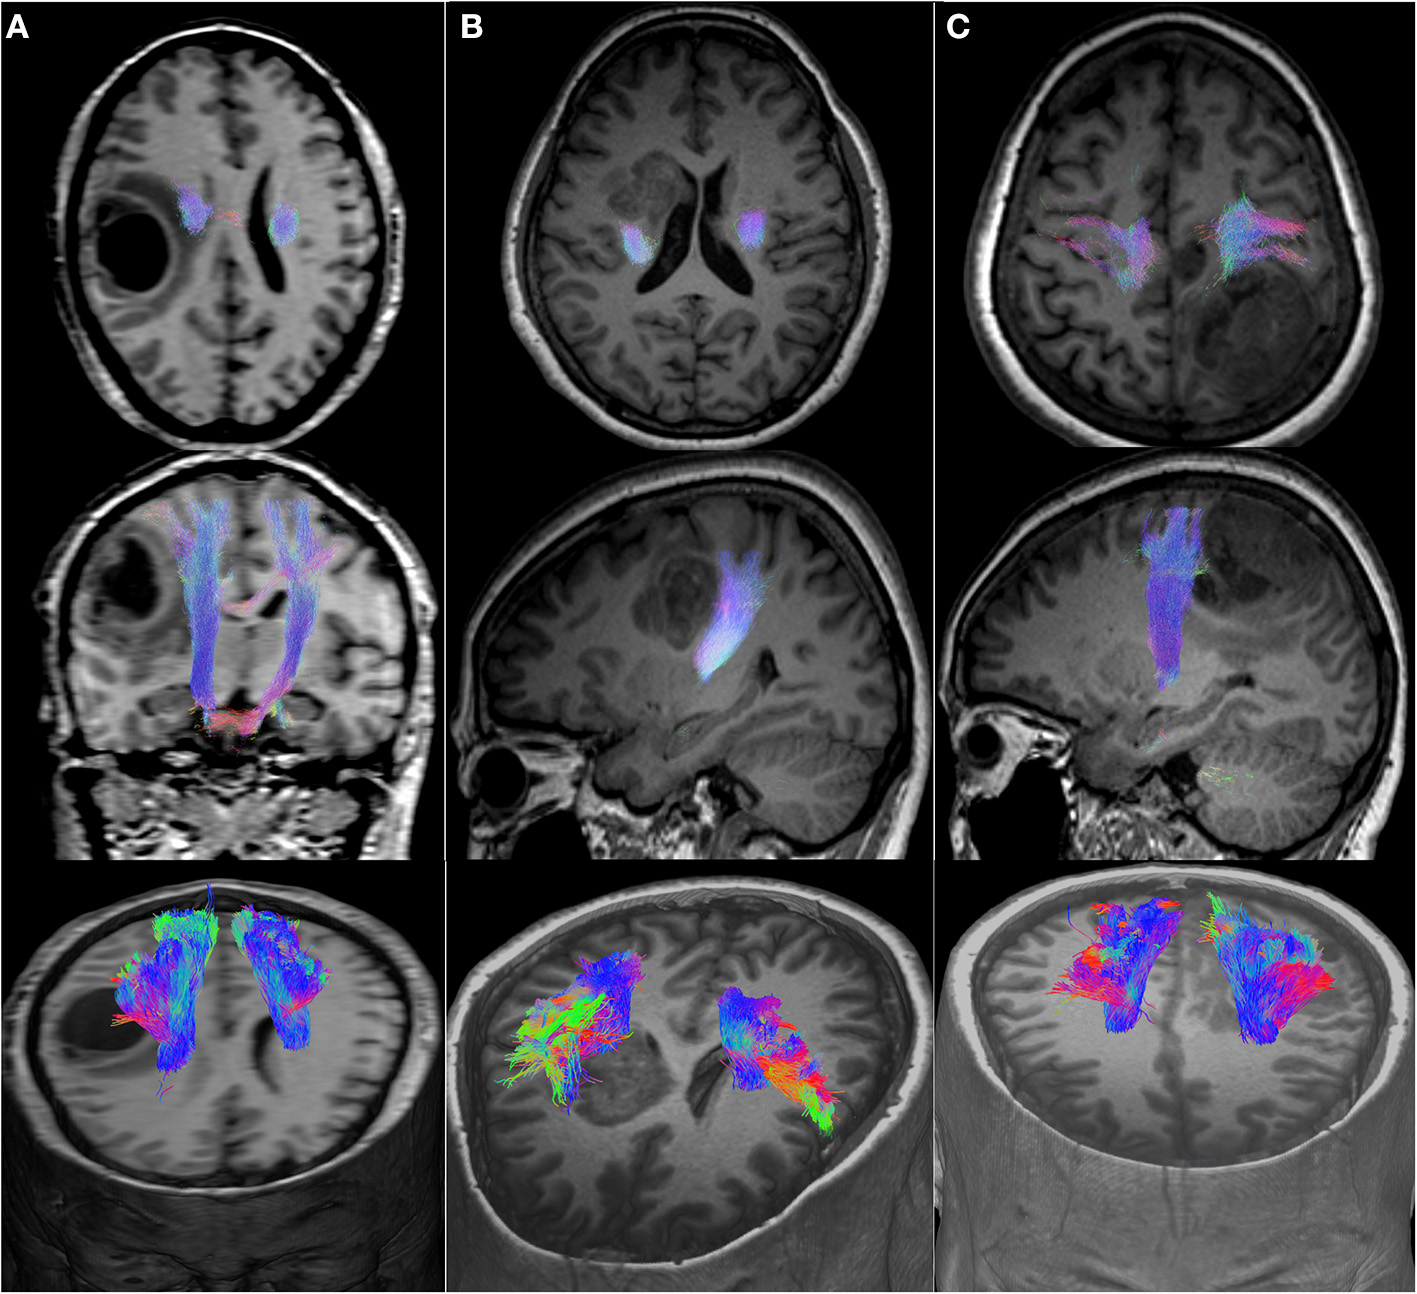

Figure 2

Motor CST displacement. (A), Axial, coronal, and 3D view of a medial displacement of the CST. (B), Axial, sagittal, and 3D view of a posterior displacement of the CST. (C), Axial, sagittal, and 3D view of an anterior displacement of the CST.

We included 12 patients, six men and eight women with a mean age of 50 years (detailed clinical and demographic data are shown in Table 1). Pathological results yielded WHO grade II glioma in four patients and WHO IV glioblastoma (GBM) in eight patients. Preoperatively, six patients were neurologically intact and six presented with mild motor deficit (grade 4/5). Gross total resection was achieved in 9 patients. The CST was identified in all patients with the two tractography approaches with different patterns of displacement (Figure 2). The CSD-Prob approach showed the CST with the characteristic fan-like configuration from the dorsal and ventral precentral gyrus to the brainstem. The Tens-DET approach showed a straight trajectory from the dorsal precentral gyrus to the brainstem missing the ventral part of the precentral gyrus. This approach also underestimated the width of the CST and showed more spurious streamlines as compared with the CSD-Prob approach (Figure 3). Among the six patients with postoperative motor deficit, the CSD-Prob approach revealed CST disruption in different degree, and this was strongly associated with the degree of motor deficit in these patients (rho = −0.88, p = 0.021). The Tens-DET approach on the other hand, showed disruption of the CST in five of the six patients with motor deficit without significant association in the motor status (rho = −0.27, p = 0.6) (Table 1, Figure 4). Finally, only the CSD-Prob identified a significant decrease in fractional anisotropy (p = 0.0006) and an increase in mean and radial diffusivity (p = 0.004, 0.005) of the CST between the ipsilesional and the contralesional hemisphere (Figure 5). There was no significant difference in the axial diffusivity with the CSD-Prob approach and with none of the diffusion scalars with the Tens-DET approach.